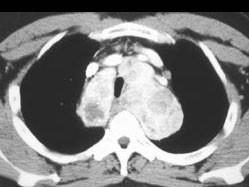

男,41岁,体检X线提示纵隔增宽,CT检查如图,请选出最可能的诊断 ( )A、间皮囊肿B、胸内甲状腺肿C、纵隔畸胎瘤D、胸腺瘤E、淋巴瘤

问题 男,41岁,体检X线提示纵隔增宽,CT检查如图,请选出最可能的诊断 ( )

选项 A、间皮囊肿 B、胸内甲状腺肿 C、纵隔畸胎瘤 D、胸腺瘤 E、淋巴瘤

答案 B